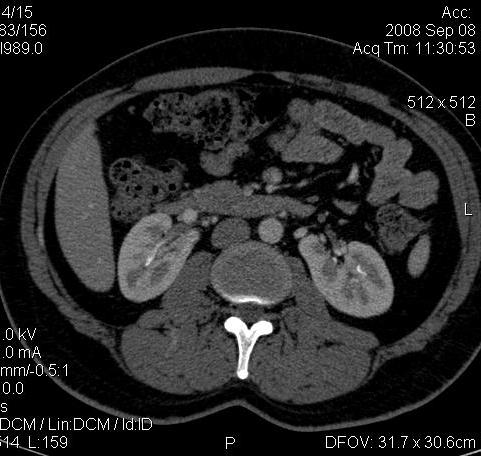

КТ Почек- подкова и уретеролитиаз

Ну ладно, раз никто больше не хочет, то отвечу свою версию - аномалия развития - подковообразная почка (horseshoe kidney).

Да красивая подковообразная почка - встречала раз 6-7.

Не вызывает сомнений. Картинка замечательная. Должно быть хорошо видно и на УЗИ.

Почечная колика; на последнем аксиальном скане чётко виден мелкий (2 мм) камень в устье правого мочеточника.